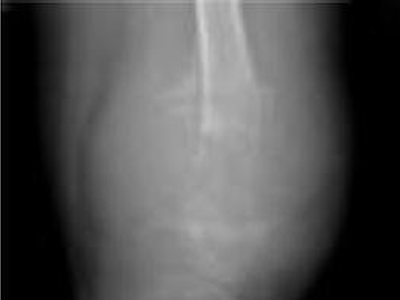

骨膜反应图 (49)

骨膜反应图 (48)

骨膜反应图 (47)